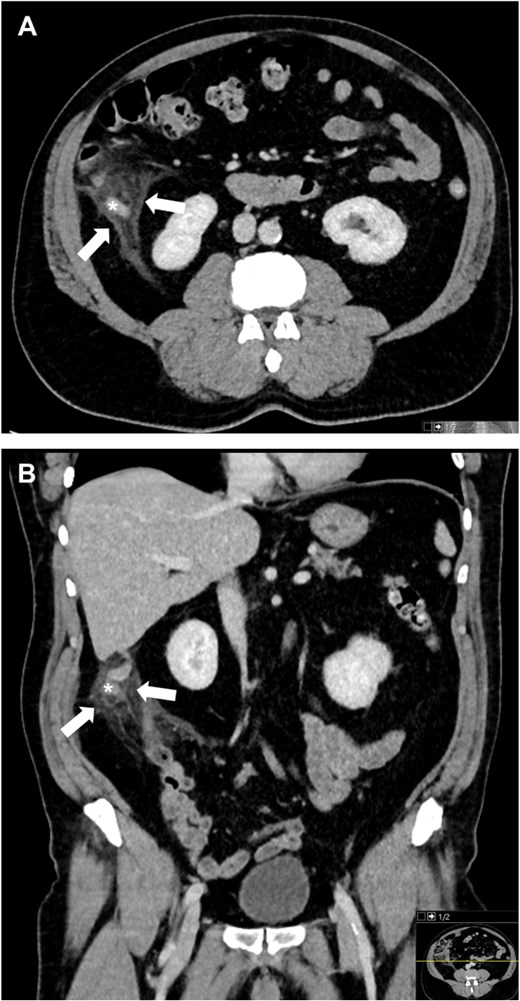

Approximately 6 weeks later, the patient returned with acute right lower quadrant pain and localized tenderness similar to his prior presentation. He was febrile on presentation and hemodynamically stable. Laboratory studies showed leukocytosis (15.1 × 109/L) and an elevated C-reactive protein level of 48 mg/L. Repeat contrast-enhanced CT confirmed recurrent uncomplicated appendicitis with a dilated, inflamed appendix (especially at the tip) and surrounding inflammatory changes, again without any appendicolith, abscess, perforation, or radiologically visible tumor (Fig. 2).

Contrast-enhanced CT images of the abdomen at the recurrence, again showing an inflamed appendix with pronounced thickening at the tip (*) and periappendiceal fat stranding (arrows) in axial (A) and coronal (B) planes.